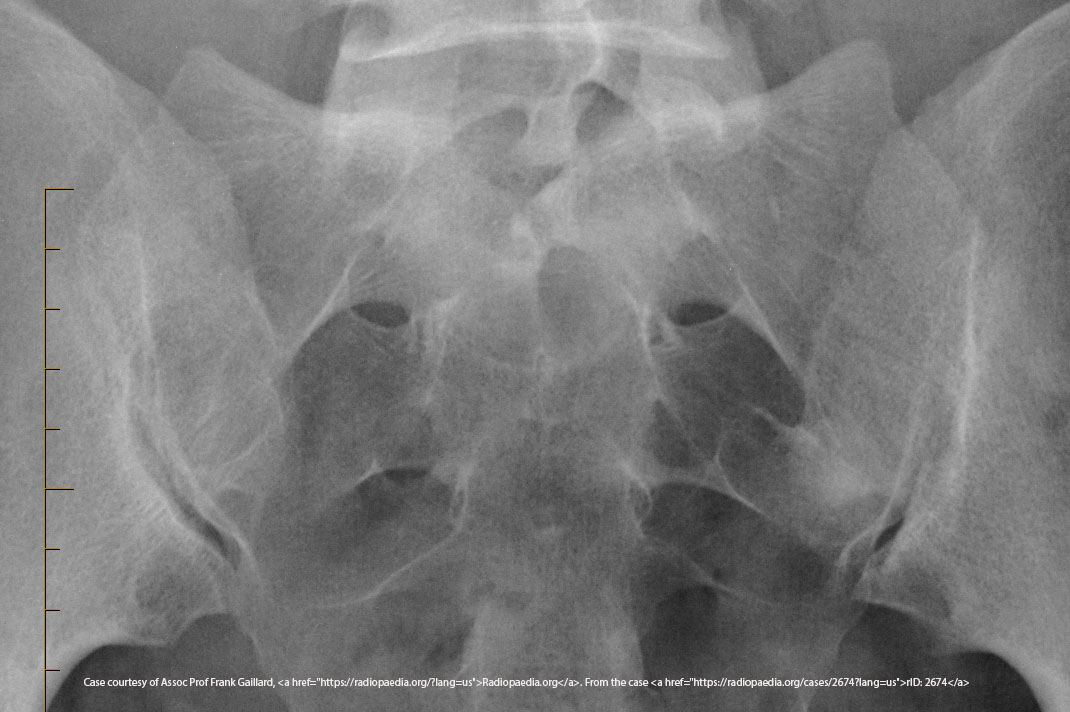

What is the CR angle for an AP axial SI joint projection (male)?

30° cephalad.

What is the CR angle for an AP axial SI joint projection (female)?

35° cephalad.

Where is the CR centered for an AP axial SI joint projection?

5–6 cm below the ASIS.

<p>5–6 cm below the ASIS.</p>

What indicates no rotation in an AP axial SI joint projection?

Symmetric SI joints.

<p>Symmetric SI joints.</p>